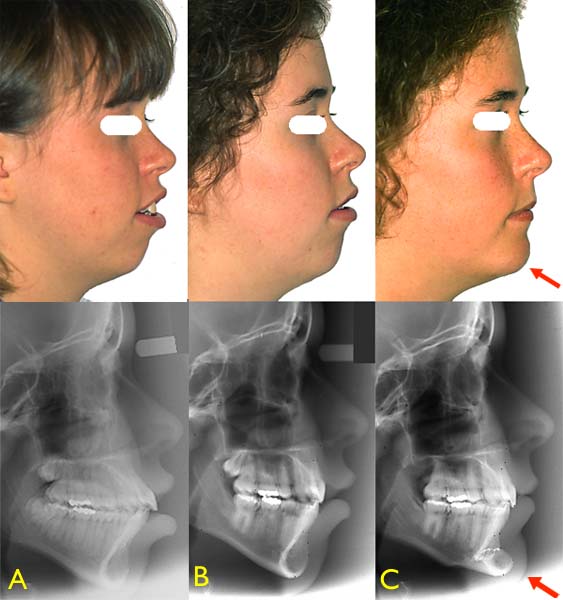

En plus de l’orthodontie ayant corrigé la position des dents, une chirurgie d’avancement du menton (génioplastie) a permis de changer le profil de cette adolescente de 18 ans. Photos : (A) Avant l’orthodontie, (B) après l’orthodontie et (C) après la génioplastie. – (Courtoisie : Dr Sylvain Chamberland, Québec)